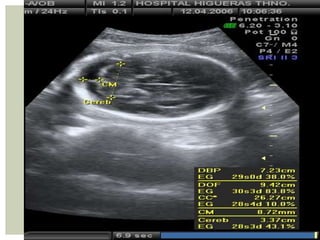

• 17.

 Debe versesiempre que DSM alcance los 16 a 18 mm  Medición de la CRL es el mejor parámetro para estimar edad gestacional  Edad gestacional:  42 + LEM en mm = Dias  6,5 + LEM en cm = Semana Rango de error +/- 5 dias